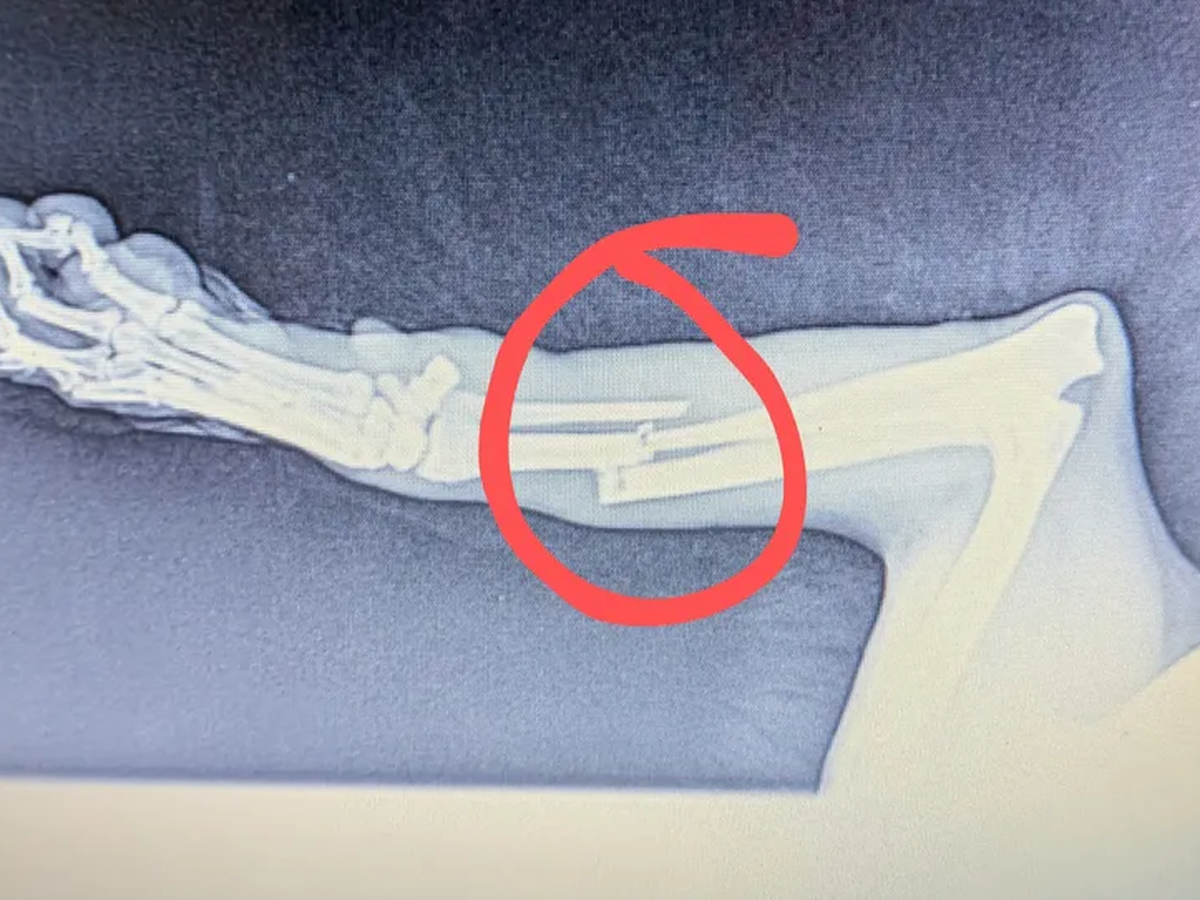

Hello, my name is Will. On Thursday, May 29th, while I was at work, I got a text from my daughter's grandma saying that when she came by to give Lady a treat, she noticed she was limping and thought that her leg was broken! So, immediately after I got off work, I rushed to see what was going on. Sure enough, Lady wasn't running up to me as she normally does. Her right front leg was completely limp, and she limped towards me in obvious pain. I inspected it as well as I could and knew then it was a break or a sprain. So, the next morning, I got a vet appointment for 1:30 to get her in and get X-rays done.

- Sure enough, it was a clean break. The veterinarian informed me that she would have to get surgery to have the bone placed right ASAP. Due to financial hardships recently, I just can't afford to get it done. So, I'm reaching out for any help possible. I've had Lady since she was 3 months old; she's 10 years old now. She's been the best dog anyone can ask for, and my kids absolutely love her! I've never done a GoFundMe or anything like this. I'm just in a bind right now and looking for any help I can get. Thank you.